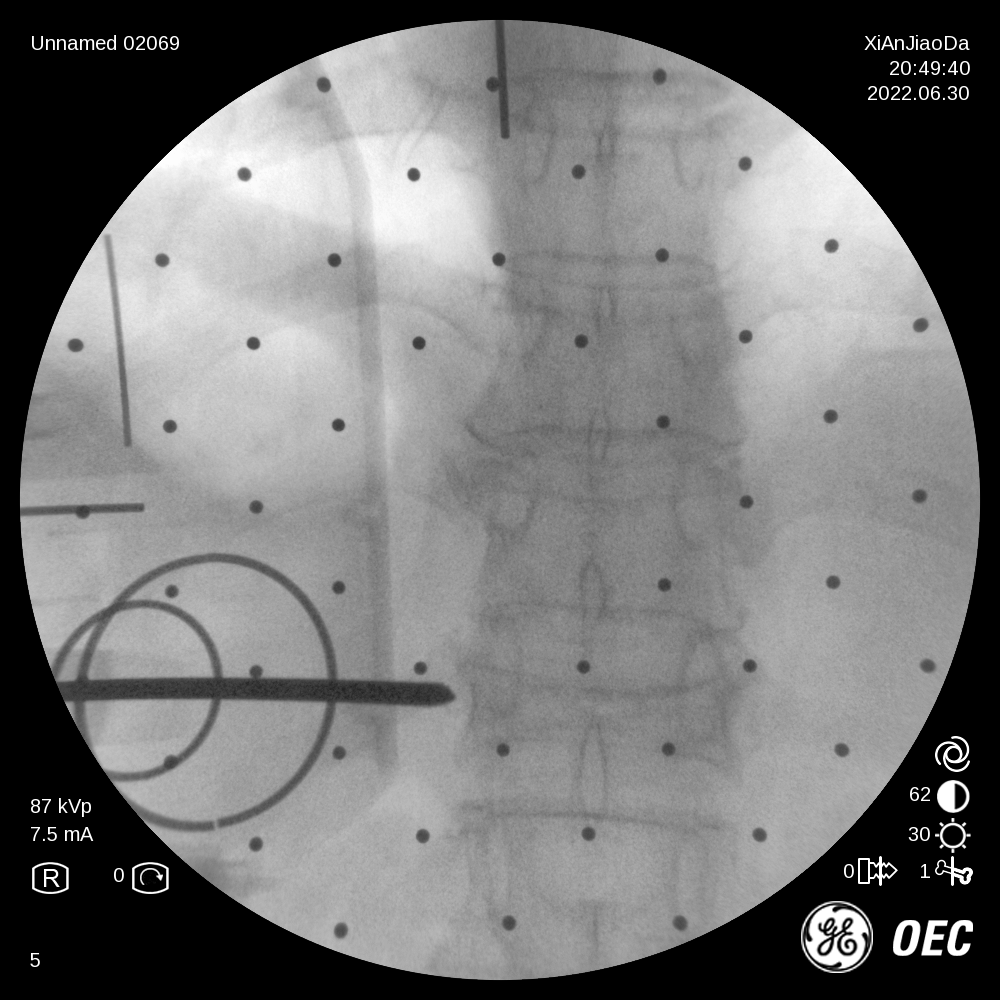

患者为一69岁女性,6月前摔倒后出现腰部疼痛伴活动受限,保守治疗后效果不佳遂来我院,经过诊断分析,该患者椎体重度压缩性骨折,重度骨质疏松致透视下骨性标志不明显,且存在轻微脊柱侧弯。王坤正主任团队最终决定运用智能化的手段,在局麻下行机器人辅助经皮椎体球囊扩张成形术,采取直观定位技术,相较其他机器人的定位导航技术,无需定位标志物,使得手术能够在全程局麻下操作,保证医生能得到患者的实时反馈,可使手术更精准、更便捷、更安全。

术前,王坤正主任团队采集患者的三维CT数据并将其导入到机器人术前规划系统中,机器人工程师与其配合确定穿刺位置、角度、深度等信息,制定出适合患者本人的个性化手术方案并在术中由机器人予以实施。

在该机器人辅助手术过程中,仅需通过正侧位进行伤椎识别,通过软件将正侧位透视图与术前规划数据的结合,即可得到病人伤椎的姿态以及实际的穿刺角度,之后机械臂根据软件参数进行精准定位,手术医生在机械臂引导下一次性进针成功,并对进针位置角度表示满意,整个过程少于20分钟,实现了手术的更精准化、高效化。相较于传统定位流程,术前规划只能保存在医生脑海中,术前与术中流程无法很好的衔接,术中穿刺依赖医生丰富的经验,对于情况复杂的病人,术中需要反复试验,导致手术时间延长、患者受辐射量增加。后续放置球囊、注入骨水泥等操作则同传统手工操作。